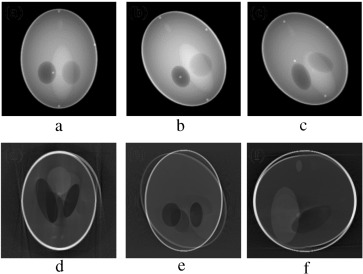

In the second stage of verification, the performance of our proposed marker-based estimator is tested with all the abrupt motion-corrupted cases of Figure 7 , Figure 8  and Figure 9 . Simulation results of actual and estimated motion parameters are listed in Table 6 , Table 7  and Table 8 . Estimated translation motion parameters are within 1.5% of actual values, and estimated rotational parameters are within 0.1% of actual values. Now, to demonstrate the efficacy of our proposed artifact mitigation technique, we apply the estimated motion parameters to the back-projection stage of the MB_FDK algorithm to reconstruct the 3D volume from the above different cases of motion corrupted projection data sets. In Figure 14 , Figure 15  and Figure 16 , we plotted the axial, coronal and sagittal slices taken from the reconstructed volume of different gradual rotational motion corrupted cases and motion artifacts compensated cases, side by side. From these figures, it can be observed that the motion artifacts originated from the gradual variations of motion have significantly been reduced by the MB_FDK approach. In Figure 17 , Figure 18  and Figure 19 , we plotted the axial, coronal and sagittal slices taken from the reconstructed volume of abrupt motion corrupted cases and motion artifacts compensated cases, side by side. From these plots it can also be inferred that the MB_FDK approach has significantly reduced the motion artifacts originated from the abrupt and large variations of motion.